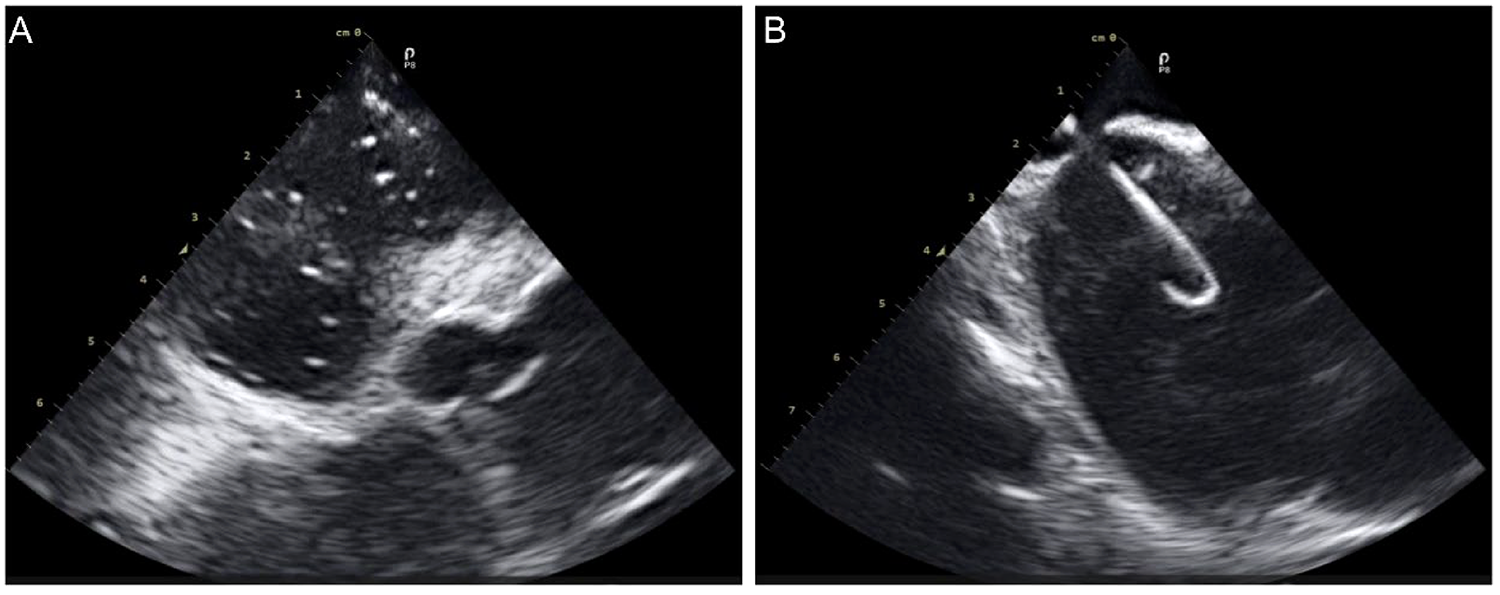

A 60-year-old woman with supraventricular tachycardia (SVT) and a 59-year-old woman with persistent atrial fibrillation (perAF). Both patients met the inclusion and exclusion criteria (Table 4) and had no contraindications related to ICE or radiofrequency ablation. All procedures were successfully performed using the Carto 3 system (Johnson and Johnson MedTech) in conjunction with commercially available electrophysiology catheters. The ICE catheters were utilized through Cordis 10 F short sheaths, and display ICE images of intracardiac anatomical structures during key operational steps (Figures 7A,B).

Figure 7

ICE images of intracardiac anatomical structures during key operational steps. (A), ICE in the right atrium captured the moment of contrast agent injection; (B) ICE revealed the transseptal sheath successfully crossing the septum.